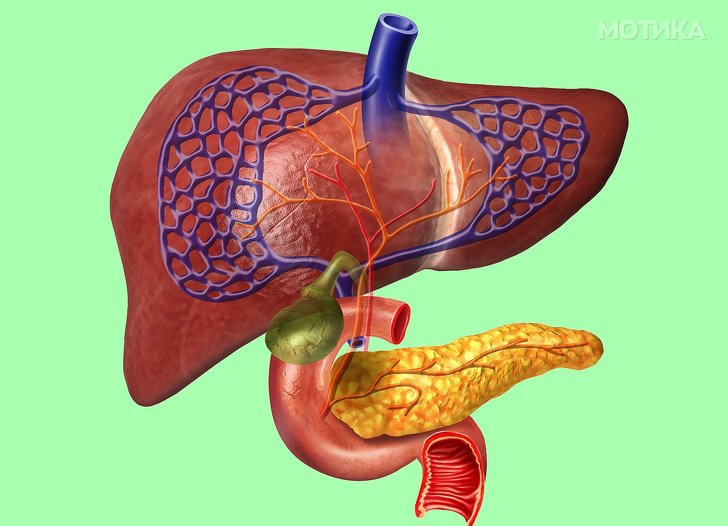

2. Црниот дроб

- Најодговорниот орган е црниот дроб. Научниците знаат за повеќе од 100 различни мали работни задачи кои ги прави црниот дроб.

- Црниот дроб може храбро да се справи со многу тешки оштетувања. Може да се регенерира, а за тоа му се потребни само 25% од ткивото.